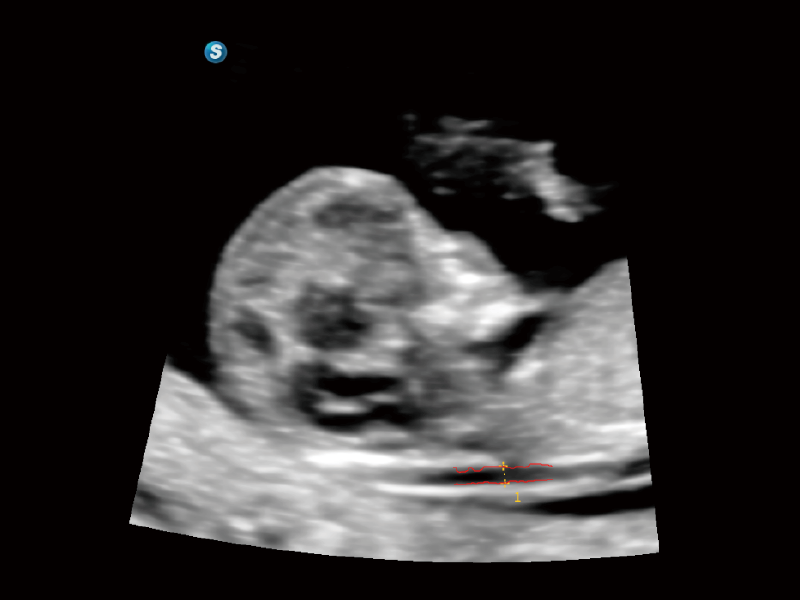

高清無損放大下的NT自動(dòng)測(cè)量